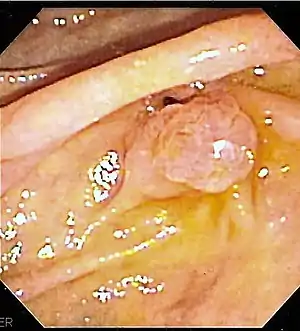

The major duodenal papilla, seen on duodenoscopy at the time of ERCP. This is the protrusion of the ampulla of Vater into the duodenum.